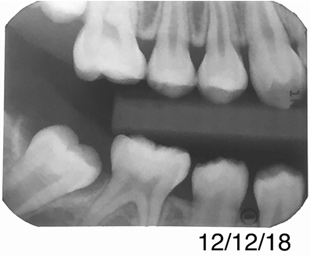

Figure 13 shows a bitewing of a 7-year-old girl with Williams syndrome who had previously required treatment under general anesthesia (GA) in a hospital setting for treatment of caries in her primary teeth. An incipient lesion on the mesial of her lower right permanent first molar, tooth No. 30, was treated more conservatively, in office, with resin infiltration, which allowed her to avoid more invasive treatment and the possible need for another GA. The lesion was arrested (Figure 14) and has been stable for over 5 years.

Fig 13. Bitewing of a 7-year-old girl. F

Figure 13

Fig 14. Same patient more than 3 years later.

Figure 14